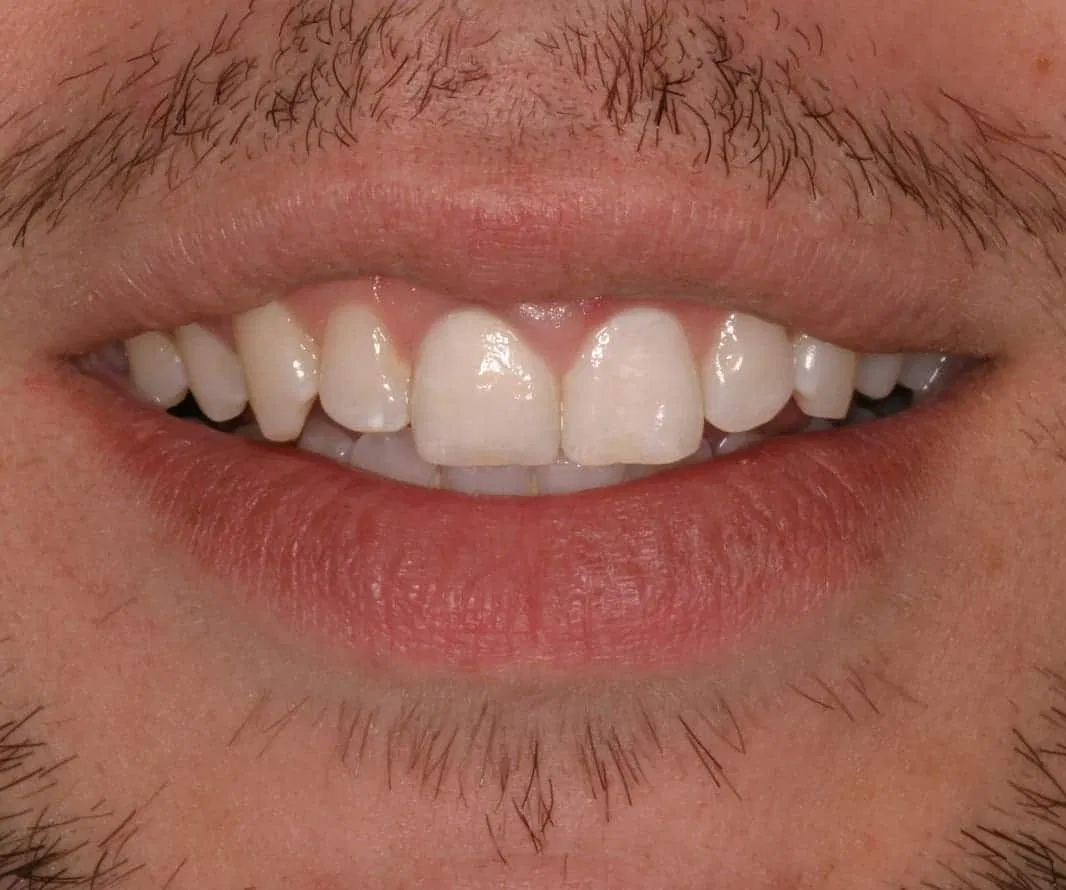

Case Study Details

Ceramic Post/Core; Ceramic Crown-Bonded

Before:Â Tooth #8 (upper right central incisor) has a history of trauma and root canal therapy. Re-treatment of the root canal filling was required.